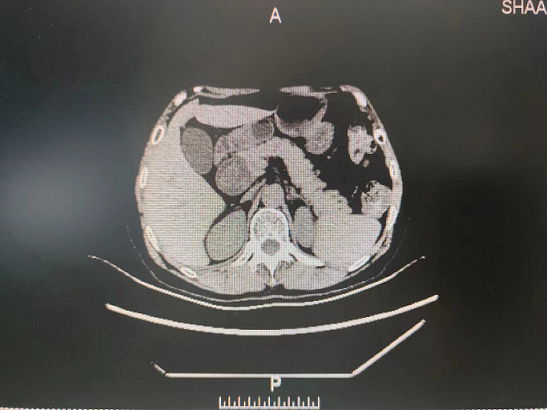

就诊,门诊以“胆总管囊肿”收住院。入院后予完善相关检查后诊断:1.胆总管囊肿(Ⅰ型)并胆总管结石2.胆管炎?。随后给予抗炎、补充电解质,营养风险评估,营养支持等治疗,组织专家进行围术期术前评估、讨论,制定手术计划方案并征得家属和本人同意后,5月15日在普外科田德福主任的带领下,在任斌副主任、杨洲明主治医师的配合下及麻醉科的协助下,对患者行胆总管囊肿切除+胆总管空肠ROU-en-Y吻合术,手术顺利,病理结果提示无癌变。术后在何慢护士长团队的精心护理下,患者第2天就下床活动,第4天进流食。术后没有发生腹腔感染、出血、吻合口漏等相关并发症,术后相关实验室检查结果无异常,5月29日患者痊愈出院。

外科第一党支部书记、普外科主任田德福主任医师表示,胆总管囊肿为先天性胆总管囊状扩张症,发病率低,可以并发结石、有癌变的可能,手术治疗是主要治疗手段。胆总管囊肿切除需要做到胆总管囊肿切除+胆总管空肠ROU-en-Y吻合术,在普外科手术中属难度较高的四级手术,开展这一高难度手术,对普外科医生来说具有很大的挑战性,不但要求具备精湛技术,更需要对患者高度负责的精神。此次手术的成功开展使得21点基本策略